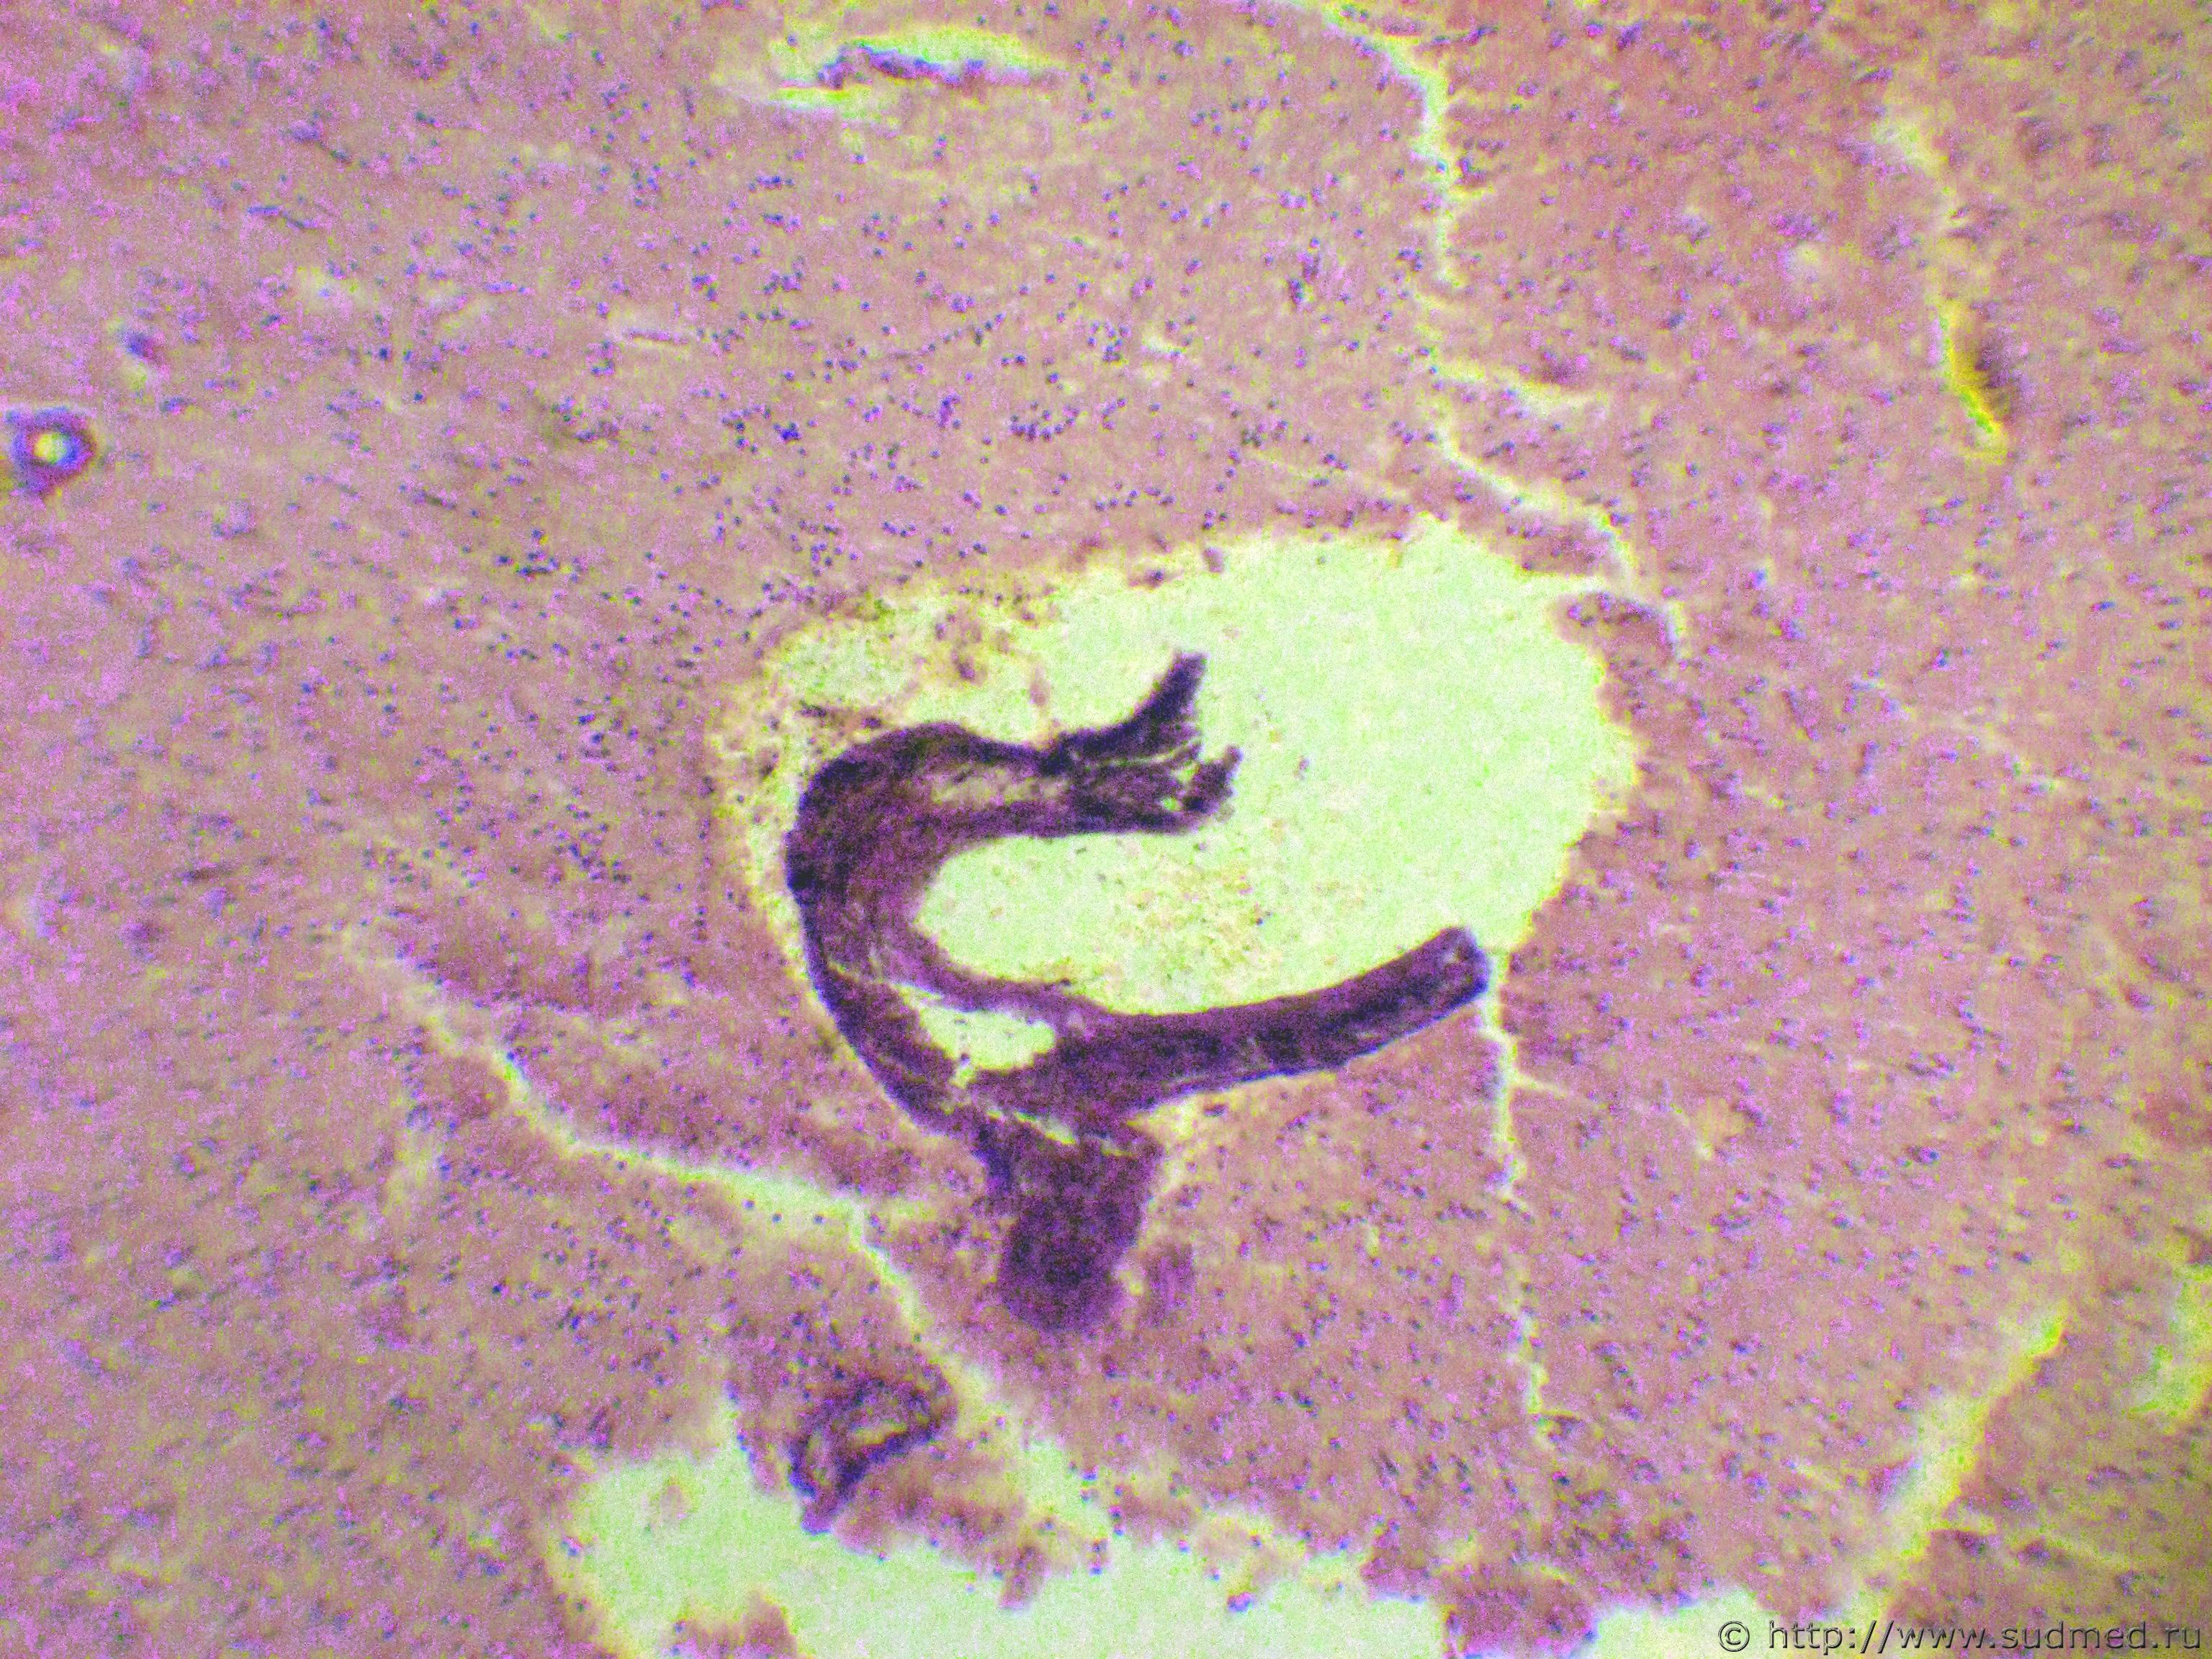

Мужчина,35 лет,умер от отравления алкоголем.В 2010г.перенёс тупую травму живота.Были разрыв печени,переломы рёбер слева.Произведена операция.

Теперь во время вскрытия трупа выявлена субкапсулярная киста селезёнки.Внутренняя поверхность кисты шероховатая с бурыми участками.В полости кисты сухие буроватые творожистые массы.Высказано мнение о посттравматической ложной кисте.

Микрофотографии.

Стенка ложной кисты.